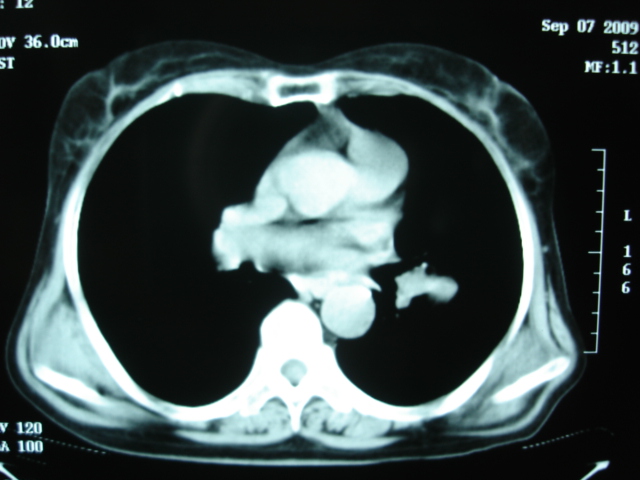

以下是引用卜一在2009-9-7 19:51:00的发言:[br][br] 1 左侧胸内甲状腺占位-多考虑甲状腺腺瘤! 2、左肺门占位-建议增强扫描以便明确性质。 3 慢支并感染! [br]

以下是引用shibing在2009-9-7 20:40:00的发言:[br]左侧胸内甲状腺占位-多考虑甲状腺腺瘤! 2、左肺门占位-建议增强扫描以便明确性质。 3 慢支并感染! [br]